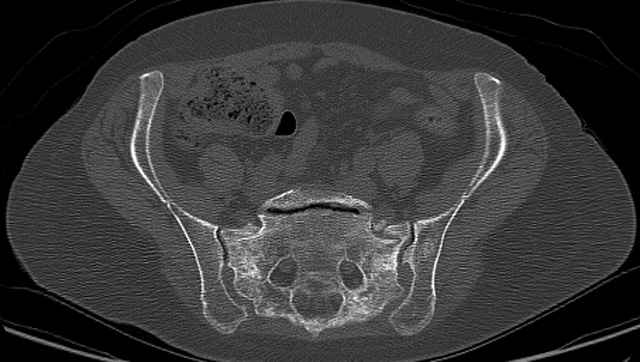

Here are a recent patient’s example slides...

3 Months After Fall

Continued Pain & Immobility

(+) Instability to Compressive Manual Exam

Pelvic CT Scan - 3 Months After Fall

Sacral Injuries

Ramus Fractures

Percutaneous Fixation

(B) Ramus-Retrograde

2 TransIliac-TransSacral

Upper Segment

mlcr